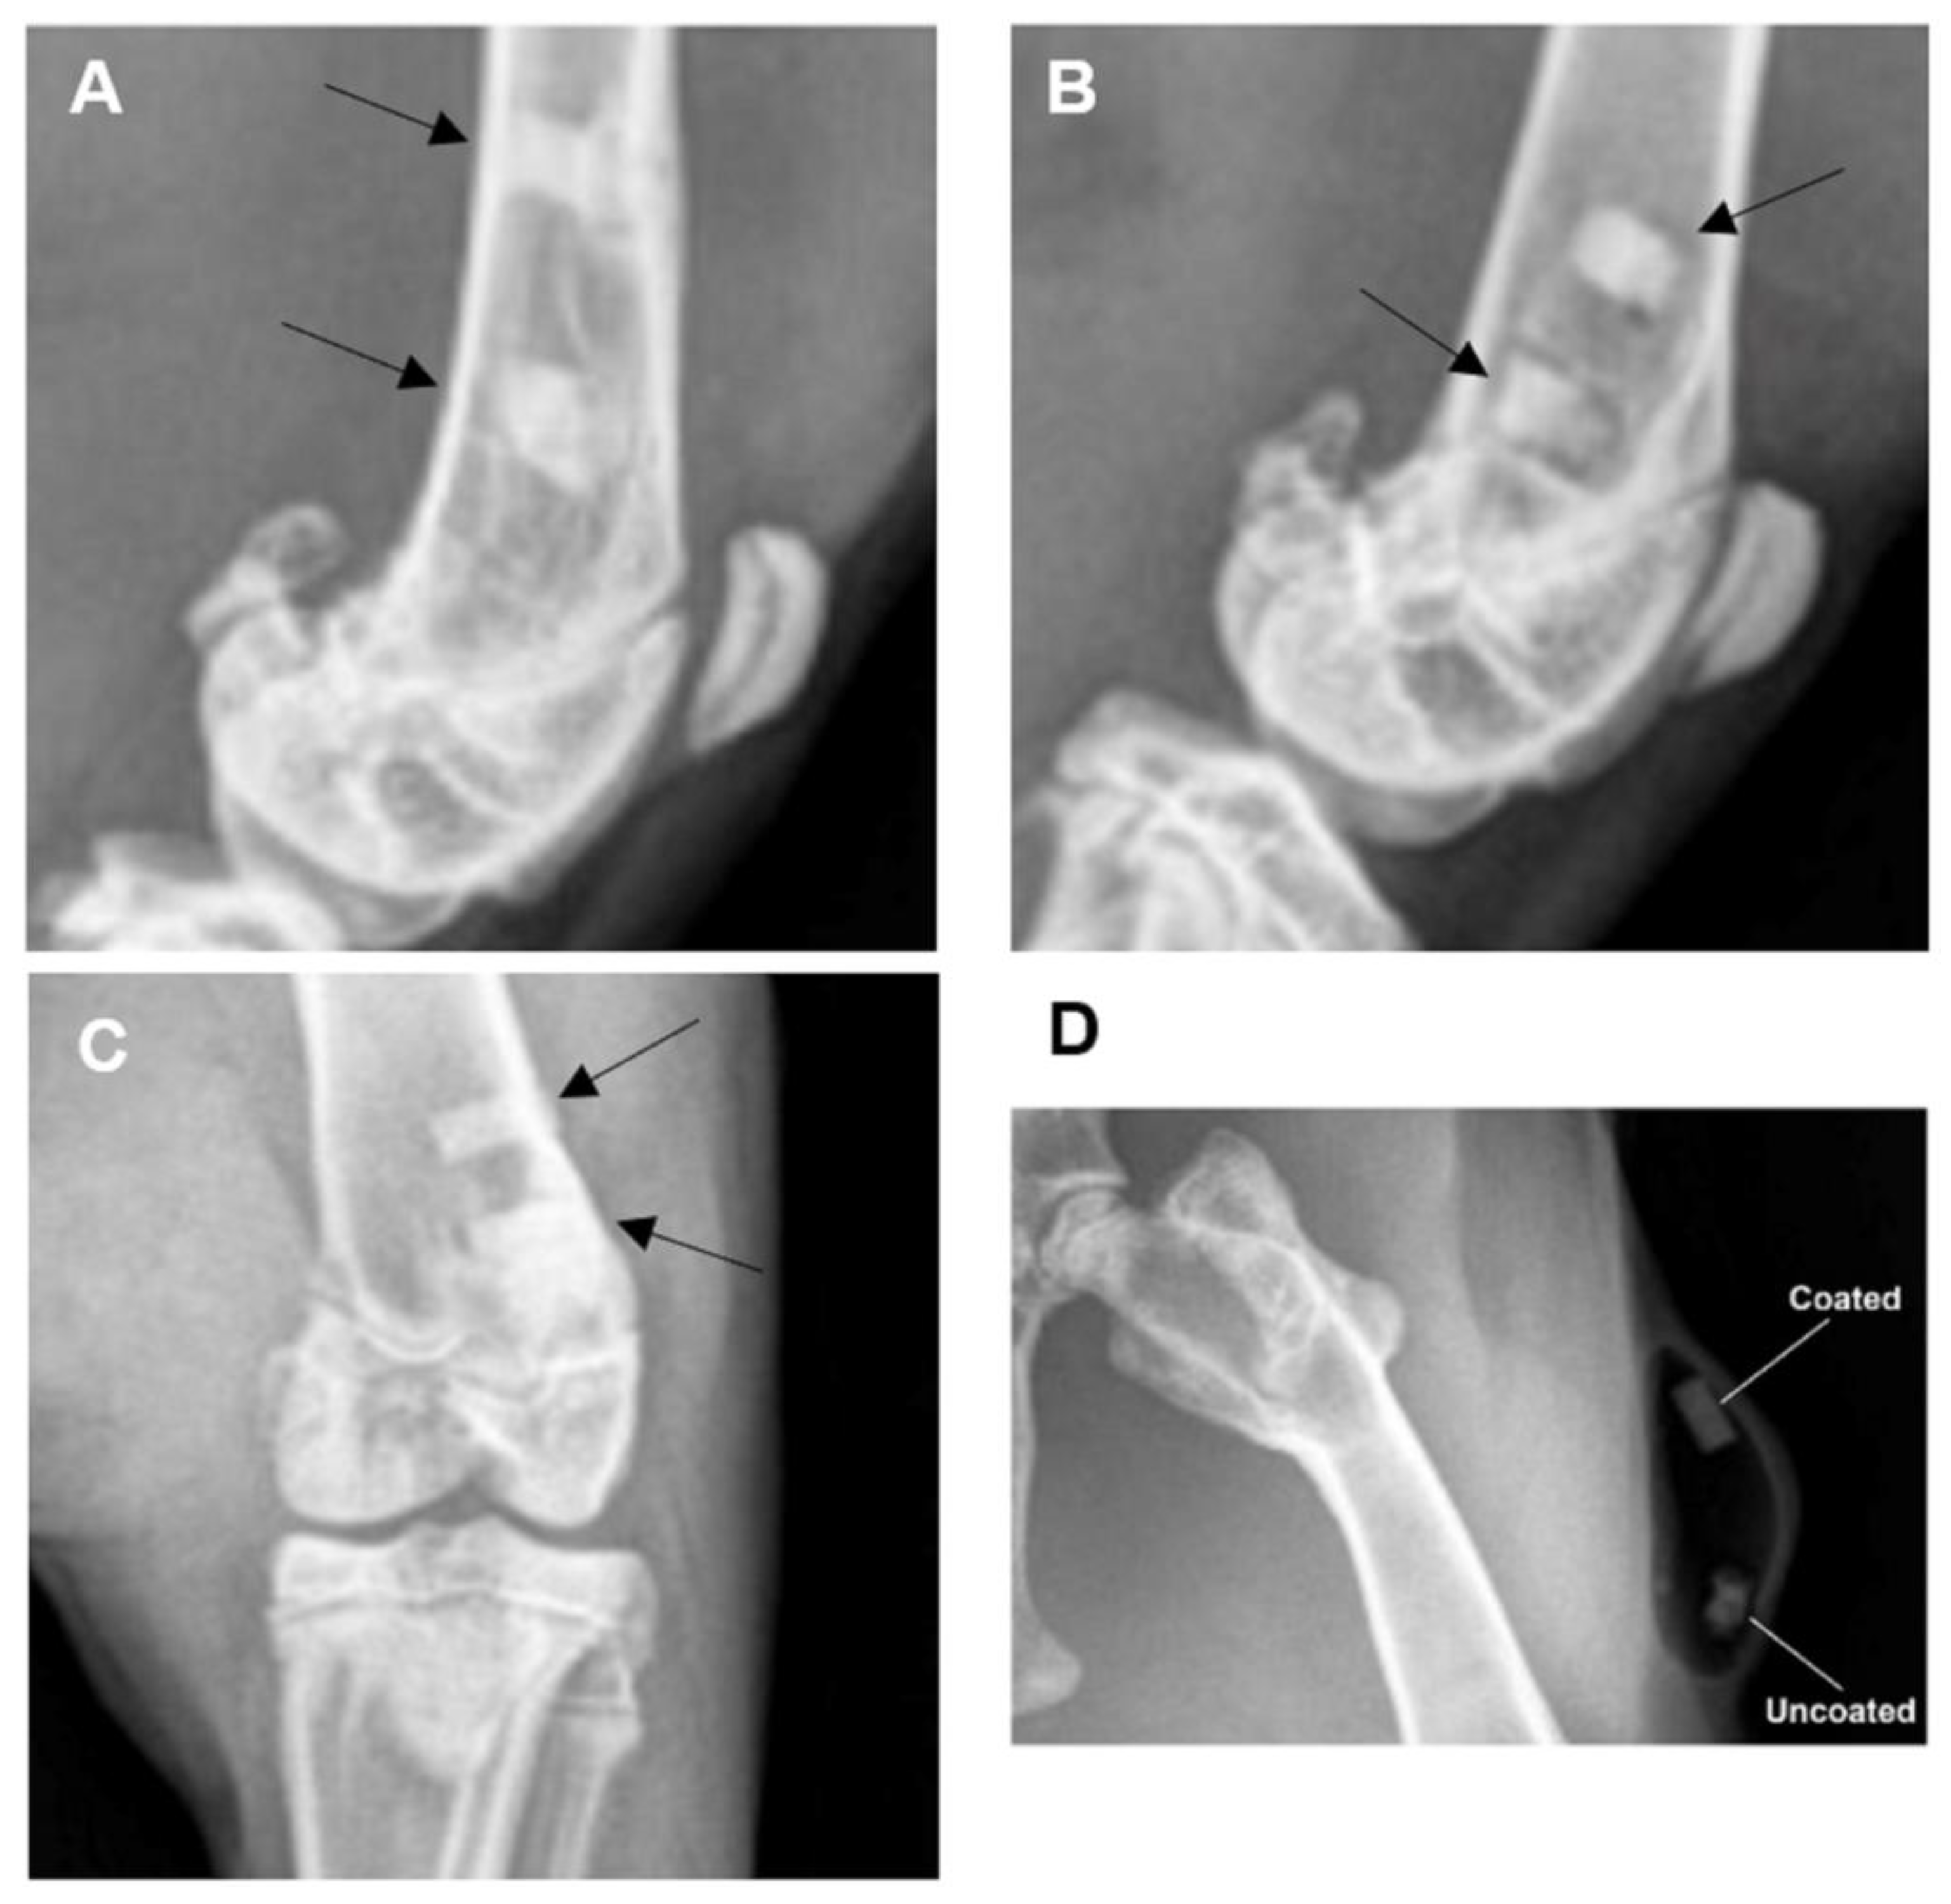

3.3.2. Radiographic Examination

3.3.3. Post-Mortem Examination Findings